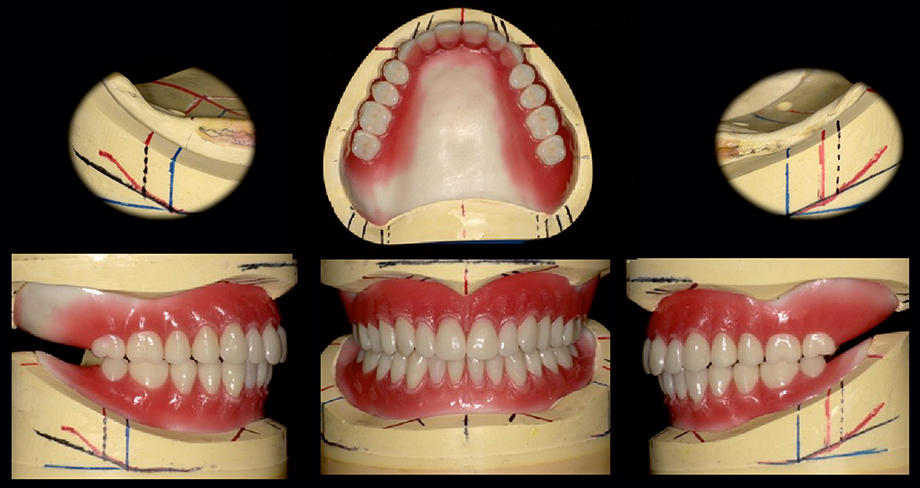

Aufstellung der Zähne unter Berücksichtigung der hydrostatischen Stabilität bei größtmöglicher Ästhetik im Frontzahnbereich und Stabilität im Seitenzahnbereich. Speziell bei der Unterkieferprothese.

Das Easy Set Up Konzept ermöglicht ein einfaches Aufstellen.

Gingivacharakterisierung zur Vervollkommnung der Ästhetik mit dem Kompositmaterial VITAVM®LC. Verwendet wurde das VITAVM®LC BASIC KIT und das VITAVM®LC GINGIVA KIT.

Nach dem Sandstrahlen und der Konditionierung des vestibulären Prothesenkunststoffs für den Verbund erfolgt der Auftrag von VITA VM LC.

Die thixotrope Paste ermöglicht eine angenehme Modellation und bietet eine optimale Standfestigkeit vor der Polymerisation.

Durch die Lichtpolymerisation wird Zeit gespart. Direkt beim Auftrag ist die Farbwirkung des Materials erkennbar. Dies erleichtert die Charakterisierung.

Das Endresultat im Mund.